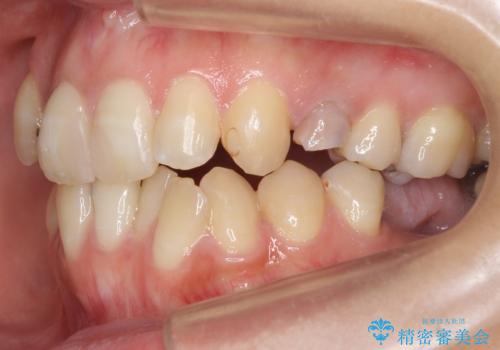

あきらめないで!!虫歯でボロボロでも大丈夫! 非抜歯矯正と虫歯、インプラント治療で見違える歯並びに。

①保存不可能な歯は抜歯しそのすき間を矯正で閉じる

②右上の親知らずは活かしてブリッジの支台にする

という、予算がかからないように歯を保存する治療計画を立てました。